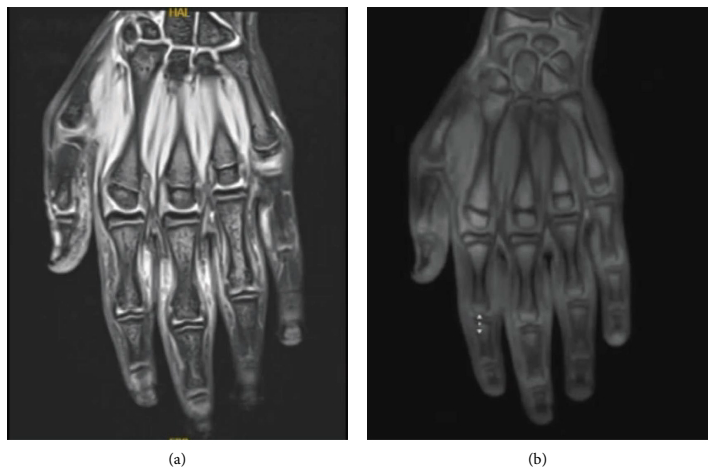

引自:Cureus. 2023;15(7):e41923.

· T1加权像:显示近端指间关节周围皮下脂肪组织内弥漫性、纺锤形低信号影,代表纤维组织增生。

· T2加权像/STIR序列:病灶可呈等或稍高信号,反映组织内可能存在的轻微

· 增强扫描:病灶可呈轻度或无强化,这与血供丰富的滑膜炎症形成鲜明对比。

· 关键阴性发现(诊断核心):无滑膜增生、无关节积液、无骨髓水肿、无肌腱腱鞘炎。这一“干净的关节”影像表现是确诊厚皮指症的强有力证据。

引自:Case Rep Dermatol Med. 2025;2025:5560071.